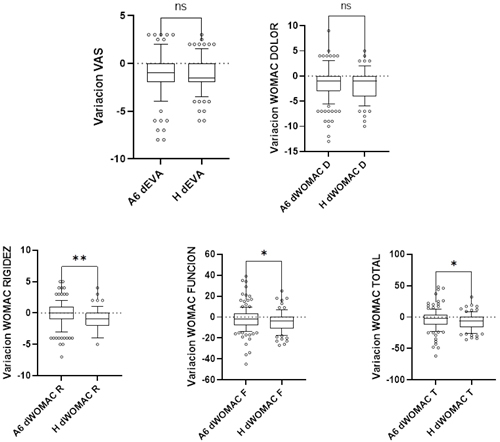

Fig. 2. Cambios de las medias absolutas de las puntuaciones del WOMAC y EVA tras el tratamiento con hialuronato a los seis meses con A y al año con H. Variación absoluta desde los datos basales. A6M: seis meses tras la infiltración con A; H12M: 1 año tras el tratamiento con H. Los diagramas de cajas y bigotes representan la media, los cuartiles superior e inferior y los percentiles 10-90 %, respectivamente. El test de Mann-Whitney fue usado para comparar los grupos con un valor alfa establecido en 0,05 como significativo. Ns: no significativo.

En la Figura 3 se muestra la comparativa de los cambios obtenidos en cada grupo después del tratamiento con AH. En relación con el dolor medido utilizando la escala EVA y con el WOMAC dolor se observa que la reducción se mantiene en ambos grupos, pero sin diferencias estadísticamente significativas (p > 0,05). Por el contrario, los cambios en los índices de WOMAC función, WOMAC rigidez y WOMAC global fueron superiores en el grupo H12M comparado con el grupo A6M (p = 0,040; p = 0,003, p = 0,043, respectivamente).

Fig. 3. Cambios de las medias absolutas de las puntuaciones del WOMAC y EVA tras el tratamiento con hialuronato a los seis meses con A y al año con H. Variación absoluta desde los datos basales. A6M: seis meses tras la infiltración con A; H12M: 1 año tras el tratamiento con H. Los diagramas de cajas y bigotes representan la media, los cuartiles superior e inferior y los percentiles 10-90 % respectivamente. El test de Mann-Whitney fue usado para comparar los grupos con un valor alfa establecido en 0,05 como significativo. Ns: no significativo.